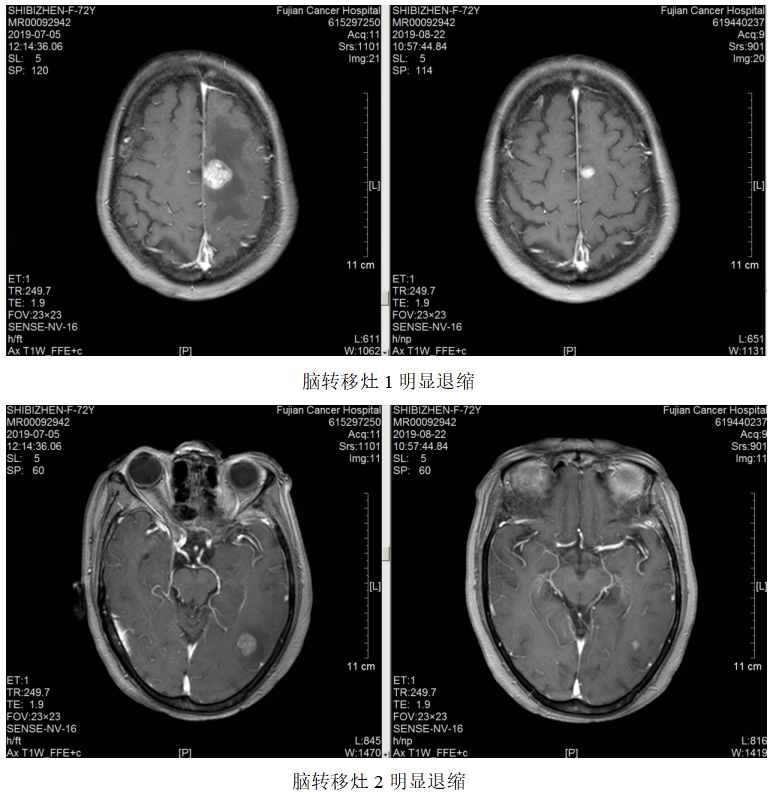

局部放疗:2019.7.23~2019.8.7予脑转移灶调强放疗DT3900CGy/13F。

疗效评估:PR。

再次放疗:2020.06.04复查颅脑MR:原左侧额、枕叶脑转移瘤较前缩小,右侧颞叶新增转移瘤,于2020.6.15-6.26予脑转移灶调强放疗DT3000CGy/10F。

继续维持治疗:新增右侧颞叶脑转移灶,配合脑转移局部放疗,其余病灶好转,继续原方案全身治疗。

该例患者为胃癌脑转移。脑转移患者的抗HER2治疗一直存在着大分子单抗和小分子TKI之争。有研究显示,由于脑肿瘤部位的血脑屏障受损,通透性要高于正常脑组织,因此曲妥珠单抗可以透过血脑屏障到达病灶部位,尤其是一些接受过脑放疗的病人更是如此。对这例患者,初诊时即存在脑转移,选择了曲妥珠单抗+化疗作为一线治疗,配合脑部放疗,达到PR效果,而后新增脑转移灶,再次放疗,继续曲妥珠单抗治疗,仍达到PR效果,患者前期予赫赛汀,后期因经济原因改予汉曲优,肿瘤依然进一步控制,患者OS>28个月。

本例报道为HER2阳性胃癌患者,初诊时已经出现脑转移。由于曲妥珠单抗是一个大分子单克隆抗体,其通过血脑屏障的能力有限,但一些学者认为如果发生肿瘤脑转移,脑肿瘤部位的血脑屏障受损,通透性要高于正常脑组织,因此曲妥珠单抗可以透过血脑屏障到达病灶部位,尤其是接受过脑放疗的患者。因此对于HER2阳性胃癌脑转移患者,推荐使用含曲妥珠单抗的抗HER2治疗方案,本例患者初诊即存在脑转移,选择了曲妥珠单抗+FOLFOX作为一线治疗,配合脑部放疗,达到PR效果后采用卡培他滨+曲妥珠单抗维持治疗,停药3个月新增脑转移灶,再次放疗,继续选用曲妥珠单抗联合卡培他滨治疗,仍达到PR效果,获得了较好的疗效。